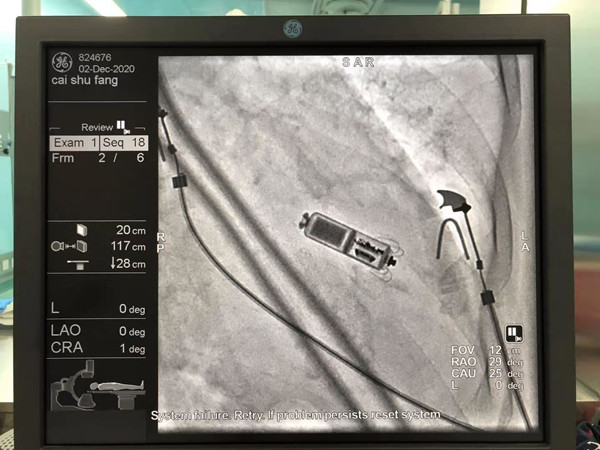

12月2日上午,心血管病院郑强荪院长带领万招飞副研究员、李永勤主任医师、曹春晖副护士长及介入电生理团队为患者实施手术,在进行局部麻醉后,通过股静脉穿刺,将起搏器通过递送系统送入到心腔内部并固定在心室间隔,蔡女士在起搏器植入中全程保持清醒状态,她可以与医生随时进行沟通。手术团队紧密配合、精心操作,成功为患者植入了Micra无导线起搏器。

和传统起搏器不同,Micra无导线起搏器有着诸多优势。在术中无需囊袋设计,可以大大减少并发症发生的风险,在胸部无伤疤、无切口。Micra体积减小了93%,仅有胶囊大小,重量仅约2g,患者在植入后感觉不到起搏器的存在,可改善患者的生活质量。Micra还拥有超强的电池续航能力预估寿命超过12年,同时兼容3.0T核磁共振扫描,可以为心脏提供持续稳定的动能。无导线起搏器手术过程时间短,植入成功率高,术后恢复情况良好,微创手术的方式也避免了传统心脏起搏器手术植入给患者带来的皮下囊袋痕迹和手术创口伤疤。